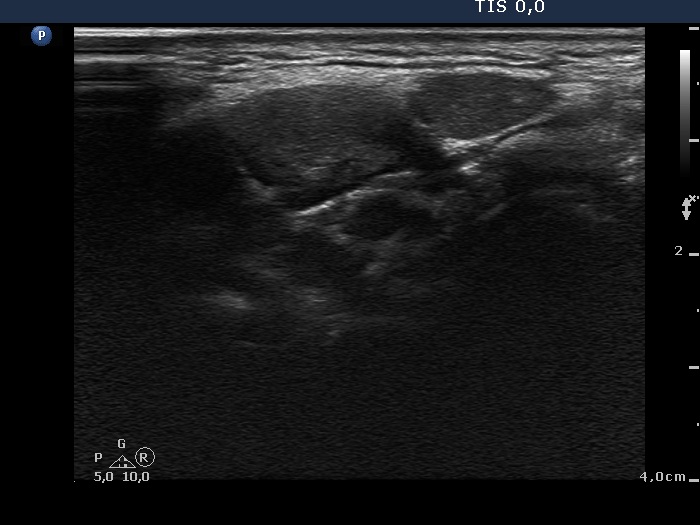

Ultrasonography: The thyroid was echonormal. There was a moderately hypoechogenic inhomogeneous nodule in the lower pole of the right lobe. There were two lymph nodes next to each other above the right thyroid in the submandibular area. The lymph nodes presented a regular hilum.

This is the typical presentation of a bacterially infected lymph node. In most of these cases we find multiple lymph nodes next or very close to each other. The presence of ill-defined hypoechogenic areas within the lymph nodes is an even more important sign of a bacterial lymphadenitis.

It is edifying to analyze the hyperechogenic figures in the thyroid lesion. While examining the patient, I interpreted these as microcalcifications. However, by preparing the case study I had to regroup these figures. These are in fact presentations of connective tissue and colloid crystals. (See the footnotes of the relevant images.)